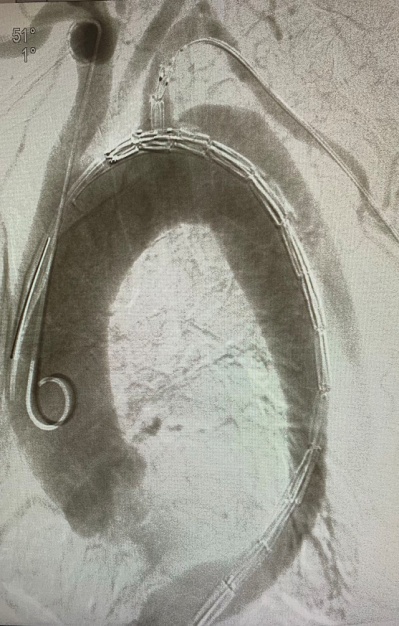

主动脉覆膜支架腔内置入术是目前主动脉夹层(Debakey Ⅲ型)治疗的首选手段,较之传统的外科开胸手术治疗,主动脉覆膜支架腔内置入术具有微创(仅需外周动脉穿刺)、术时短、成功率高、病死率低和并发症低等优点。